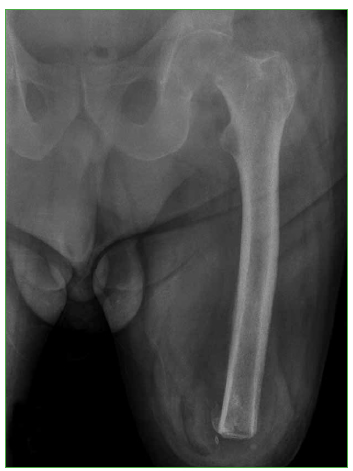

Hip fractures in patients with ipsilateral limb amputations are uncommon injuries that pose a challenge for orthopedic surgeons. In this article, we present our experience in the treatment of a 63-year man with left transfemoral amputation, who suffered a left femoral neck fracture after a fall from standing height. Proper placement of the prosthesis is essential to achieve good postoperative clinical outcomes. A Steinmann pin was inserted into the greater trochanter to facilitate exposure and component placement. No clinical or radiological complications were detected in a 15-month follow-up. We believe that the correct placement of a Steinmann pin is a good alternative that provides adequate control over the extremity when performing an arthroplasty, thus reducing the risks for prosthesis displacement and shortening the surgical time.